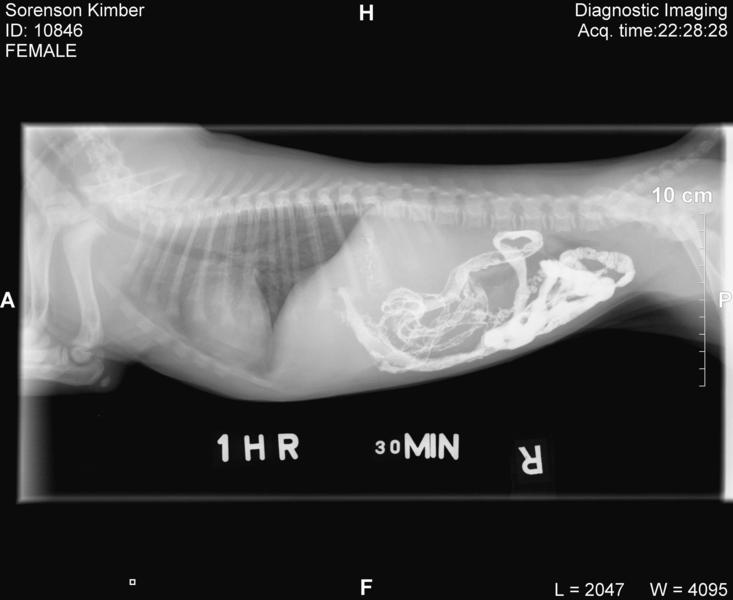

Kimber's trip to emergency

• Click to enlarge image Sorenson Kimber Jordan_CR_20090125_222738_10.jpg

If you look by her front sholder you can see her microchip implant.  Pretty cool hey!